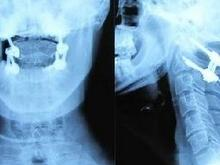

♥伴齿状突骨折的寰枢椎前脱位

创伤性寰-枢椎不稳定是指该部骨和韧带结构遭受暴力损伤,丧失正常功能和稳定作用,可导致寰枢椎脱位或半脱位[1],引起神经压迫症状。